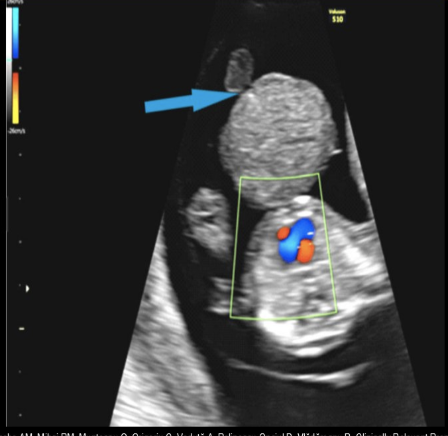

this is a routine 1st trimester scan. this shows

a) omphalocele + ectopia cordis

b) cloacal extrophy

c) normal midgut herniation

d) vanishing twin syndrome